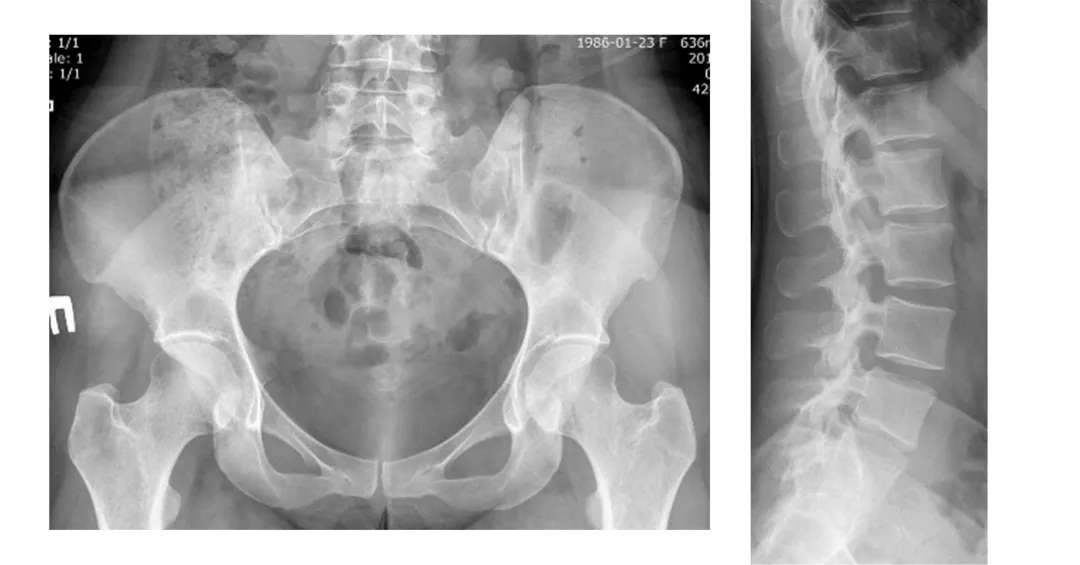

Аксиальный ПсА3

Аксиальное поражение при целенаправленном обследовании пациентов с ПсА выявляется достаточно часто — до 70% случаев; задержка в диагностике связана, как правило, с непостоянным характером воспалительной боли в спине. При вовлечении осевого скелета в воспалительный процесс при ПсА наблюдается более тяжелое течение заболевания, более высокая активность, чем у пациентов, имеющих только периферическое поражение, при этом наблюдаются более грубые структурные изменения.

В соответствии с Национальными клиническими рекомендациями по ПсА рентгенография таза и позвоночника для диагностики аксиального поражения показана всем пациентам с ПсА7.

Поражения осевого скелета при ПсА имеют свои особенности3.

Асимметричные синдесмофиты, часто малочисленны, имеют больший размер и объемную форму.

Image

Frame 24061581.png

Характерными для ПсА являются паравертебральные оссификаты (см. рис.). Они имеют вытянутую форму, расположены в мягких тканях вдоль оси позвоночника, по одной из латеральных поверхностей тел позвонков и межпозвонковых дисков. В начальной стадии они не связаны костным основанием с телами позвонков. В более поздние сроки оссификаты соединяются с телами позвонков в местах прикрепления передней продольной связки позвоночника.

Frame 24061578 (2).png